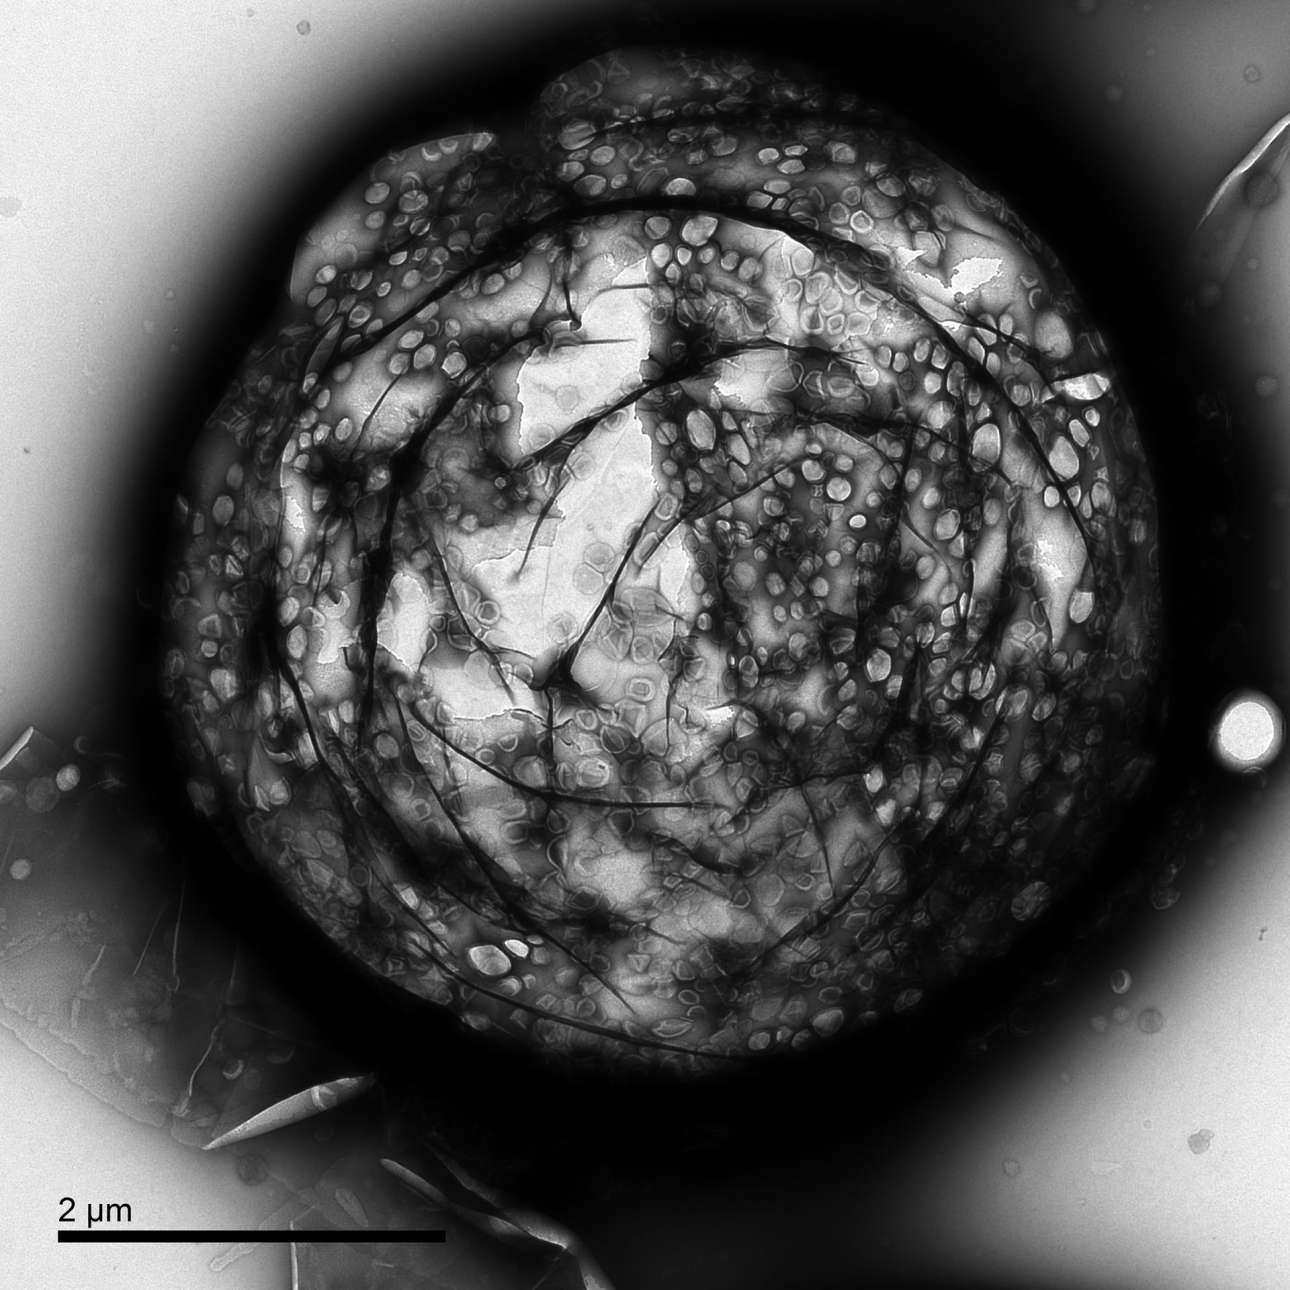

Πρώτο Βραβείο κατηγορία Καινοτομία. Οι ερευνητές του Πανεπιστημίου της Οξφόρδης αποφάσισαν αντί για μικρομπόλ να χρησιμοποιήσουν μικροφυσαλίδες για να εξουδετερώσουν καρκινικούς όγκους. Ο πυρήνας των φυσαλίδων έχει αέριο και ένα βιοσυμβατό κέλυφος ώστε αυτές οι φυσαλίδες να μπορούν να μεταφέρουν αποτελεσματικά αντικαρκινικά φάρμακα σε όγκους. Οι φυσαλίδες αυτές έχουν επίσης την ικανότητα να αυξάνουν την ποιότητα διαγνωστικών απεικονίσεων στις οποίες χρησιμοποιούνται υπέρηχοι. Στην φωτογραφία εικονίζεται μια φυσαλίδα στην οποία έχει τοποθετηθεί μια επίστρωση λιποσωμάτων που περιέχουν αντικαρκινικό φάρμακο

Estelle Beguin/University of Oxford/EPSRC Photography Competition 2017